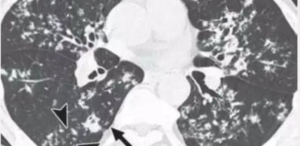

• ⁠ ⁠focal or patchy heterogeneous consolidation involving the apicoposterior segments of the upper lobes and the superior segments of the lower lobes

lateral view of the same patient, the typical location of the apicoposterior segment

• ⁠ ⁠Xray showing cavitatory consolidation in right upper lung zone and multiple ill-defined nodules in both lungs

CAVITATION AND TREE IN BUD SIGN IS INDICATIVE OF AN ACTIVE DISEASE PROCESS AND USUALLY HEALS S A LINEAR OR FIBROTIC LESION.